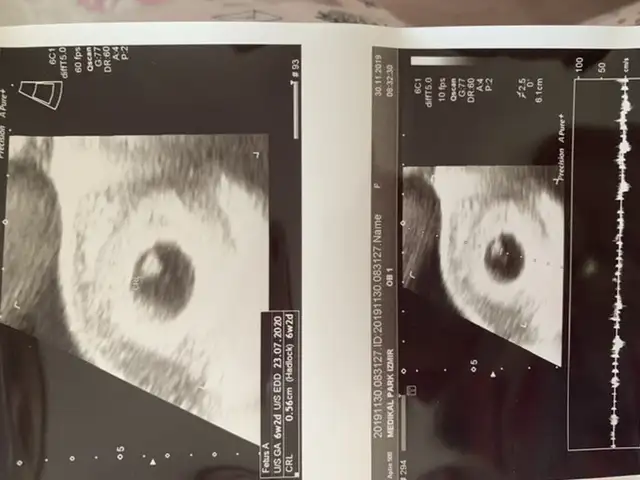

Öğrendiniz mi cinsiyetiniBu 6 haftalık olan

Eki Görüntüle 2580903